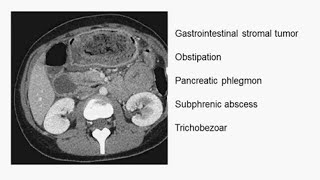

The N Engl J Med image of the week is an abdominal transverse CT. We observe a stomach filled with dark matter. You are ...